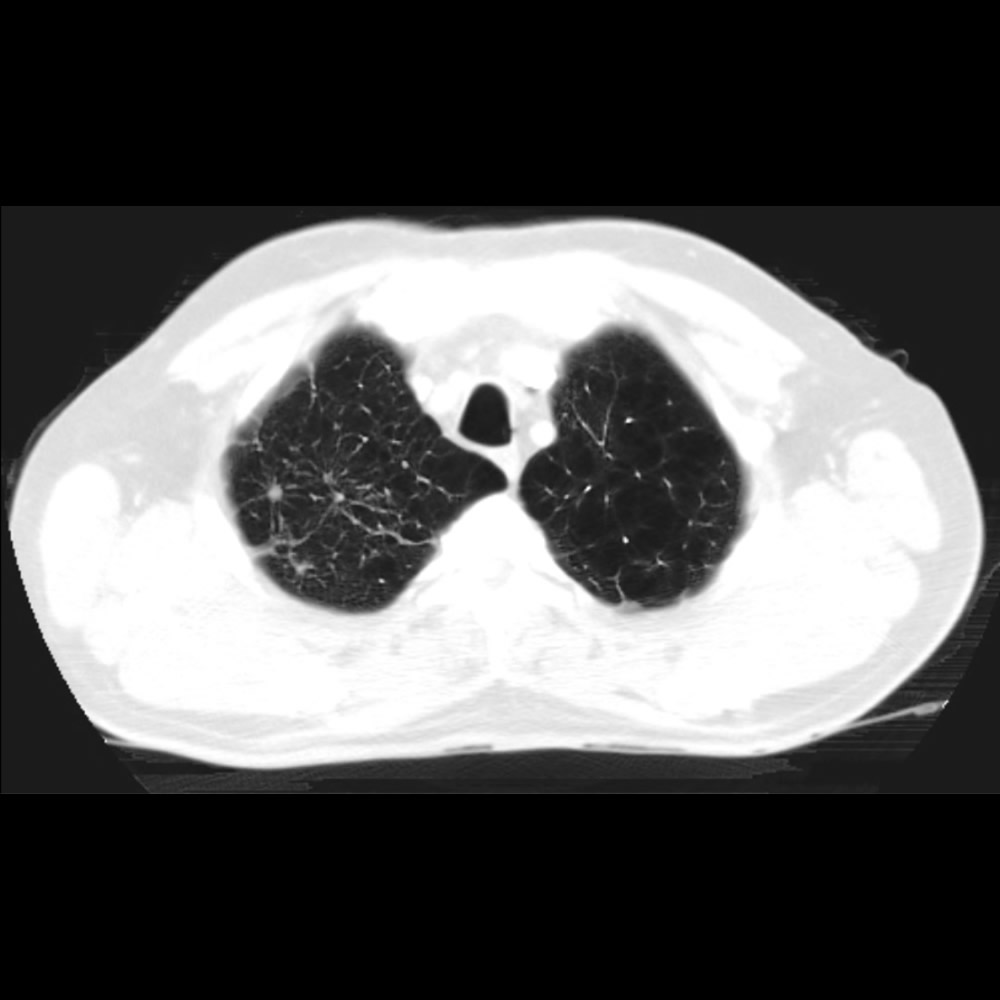

Noviembre 2024. Sanatorio de la Cañada Masculino 76 años. Control tomográfico anual de nódulo pulmonar